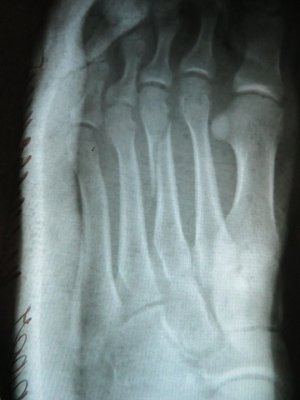

Сегодняшний рентгеновский снимок прилагаю.

• IMG_13 45.jpg

IMG_13 45.jpg

132,5 КБ · Просмотры: 720

• IMG_134 6.jpg

IMG_134 6.jpg

87,9 КБ · Просмотры: 638

По данному рентгеновскому снимку действительно показано оперативное лечение